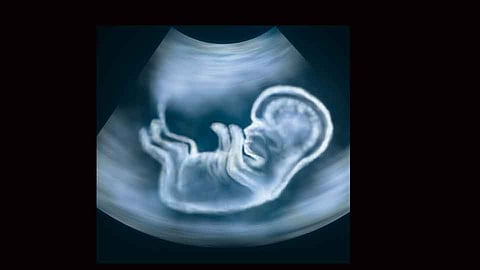

जालना - जिल्ह्यात बेकायदेशीरपणे गर्भलिंगनिदान व गर्भपात होत असल्याची माहिती नागरिकांनी दिल्यास त्यांना एक लाख रुपयांपर्यंत बक्षीस देण्यात येईल, अशी माहिती जिल्हा शल्यचिकित्सक डॉ. प्रताप घोडके यांनी दिली. शिवाय माहिती देणाऱ्याचे नाव गोपनीय ठेवण्यात येणार आहे.

जिल्ह्यात अवैध गर्भपात थांबविण्यासाठी नागरिकांनी गर्भलिंग निदान केंद्राची माहिती १८००२३३४४७५ या हेल्पलाईन क्रमांकावर द्यावी. माहिती देणाऱ्याचे नाव गोपनीय ठेवले जाईल, असे आवाहन जिल्हा शल्यचिकित्सक डॉ. घोडके यांनी केले.